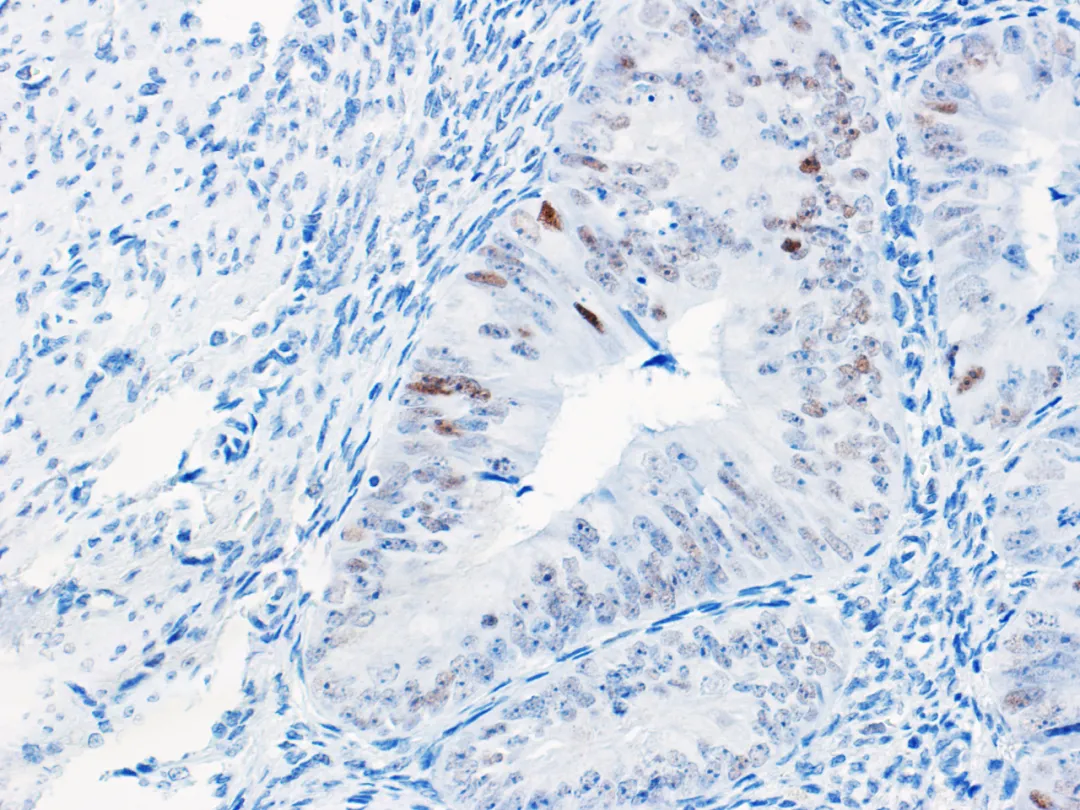

p53 immunohistochemistry helps differentiate ovarian high-grade serous carcinoma (as shown in Figure 1) from low-grade serous carcinoma (as shown in Figure 2). This diagnostic classification is significant for clinical treatment: regarding treatment plans, high-grade serous carcinoma (Tp53gene mutation) — p53 immunohistochemistry results are mostly abnormal expression states, requiring at least 6 cycles of platinum-based neoadjuvant therapy after surgery. Low-grade serous carcinoma (Tp53gene normal) — p53 shows wild-type expression, and neoadjuvant therapy of 3-6 cycles is administered only for stage Ic or above after surgery. High-grade serous carcinoma with BRCA1/2 mutations can be treated with relevant inhibitors, while low-grade serous carcinoma may be treated with hormone therapy; specific targeted therapy drugs also differ for serous carcinomas of different grades.

Figure 2. Low-grade ovarian serous carcinoma – Wild-type p53 normal expression